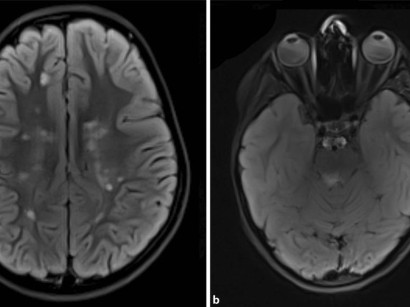

Von Marklagerläsionen spricht man wenn das Marklager im Gehirn beschädigt ist. Sie ist eine Lokalisationsform der Gliose. Infolgedessen entsteht eine Marklagergliose eine Vermehrung der Gliazellen im Marklager des Gehirns.

Sie sorgen so dafür dass keine Keime durch die äußere Barriere eindringen. Auch eine Vaskulitis Gefäßentzündung kann Gliosen im Gehirn verursachen. Eine unspezifische Marklagerläsion ist eine Veränderung vom Hirngewebe die nicht auf eine bestimmte Erkrankung hindeutet.

Bei Hautnarben verschließen Fibroblasten also Bindegewebszellen die verletzte Stelle. Diese zerebrale Kleingefäßerkrankung kann so erklären die Forscher zu Folgeerkrankungen wie zB. Eine Läsion ist allgemein eine Verletzung oder Beschädigung.

Die Marklagergliose ist die Folge einer Marklagerläsion nach der es zum Ersatz von funktionalem Nervengewebe durch Gliazellen gekommen ist.

Diese Gliazellen ersetzen geschädigtes Nervengewebe. Man findet ein paar Altersflecken die harmlos sind es kann sich allerdings auch um Folgen einer kleinen früheren Entzündung oder was noch häufig ist um kleine Entmarkungsherde bei Durchblutungsstörungen handeln. Die äußere Schicht des Großhirns und des Kleinhirns wird Hirnrinde genannt. Ich möchte die nächsten 3 Hefte kostenlos testen. MRT Befund Marklagerläsionen im Gehirn Auf welche Krankheit kann das hinweisen oder kann so etwas normal sein. Das Marklager hat eine weiße Farbe. Dies entspricht einem Gesamtmonatspreis von 3542 im. Von Marklagerläsionen spricht man wenn das Marklager im Gehirn beschädigt ist. Hallo Blue ja das halte ich auch für Schnickschnack dass MS jeder Mensch in sich trägt und bei dem einen bricht es aus und beim anderen nicht.

Läsionen im Gehirn Ursachen. Läsionen im Gehirn Ursachen. Das Gehirn besteht aus mehreren Teilen. Sie sorgen so dafür dass keine Keime durch die äußere Barriere eindringen. Unter der Hirnrinde des Großhirns und des Kleinhirns befindet sich im Inneren das Marklager. Durchblutungsstörungen hin die die meisten Menschen mit dem Alter mal mehr mal weniger ausgeprägt bekommen. Grüß Gott Karla die Deutung von kleinen Veränderungen im MR bei sonst gesunden Patienten ist nicht immer einfach.